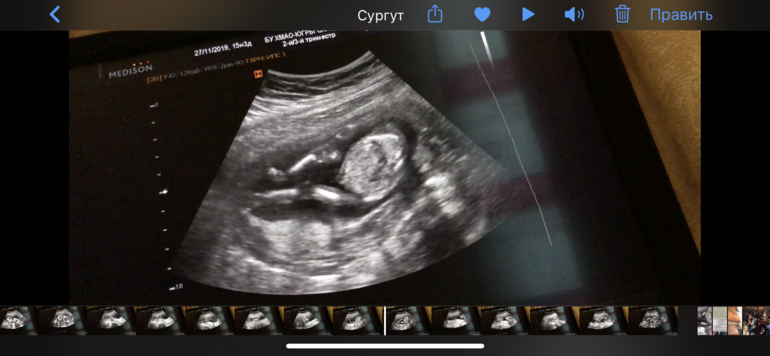

Пол малышаА давайте посмотрим, кто же это может быть? Пацан или девочка? Врач пол не сказала, сказала ждите скрининг

Мой по видео видно, что когда врач пытается пол разглядеть, он тут же убегает 😂

Не, она его там вертела, крутила, искала, сказала «я подозреваю, но это не точно» я щас же всю ночь буду сидеть это двух минутное видео пересматривать, искать 😂 ну не верю я блин, что девочка 😂😂😂